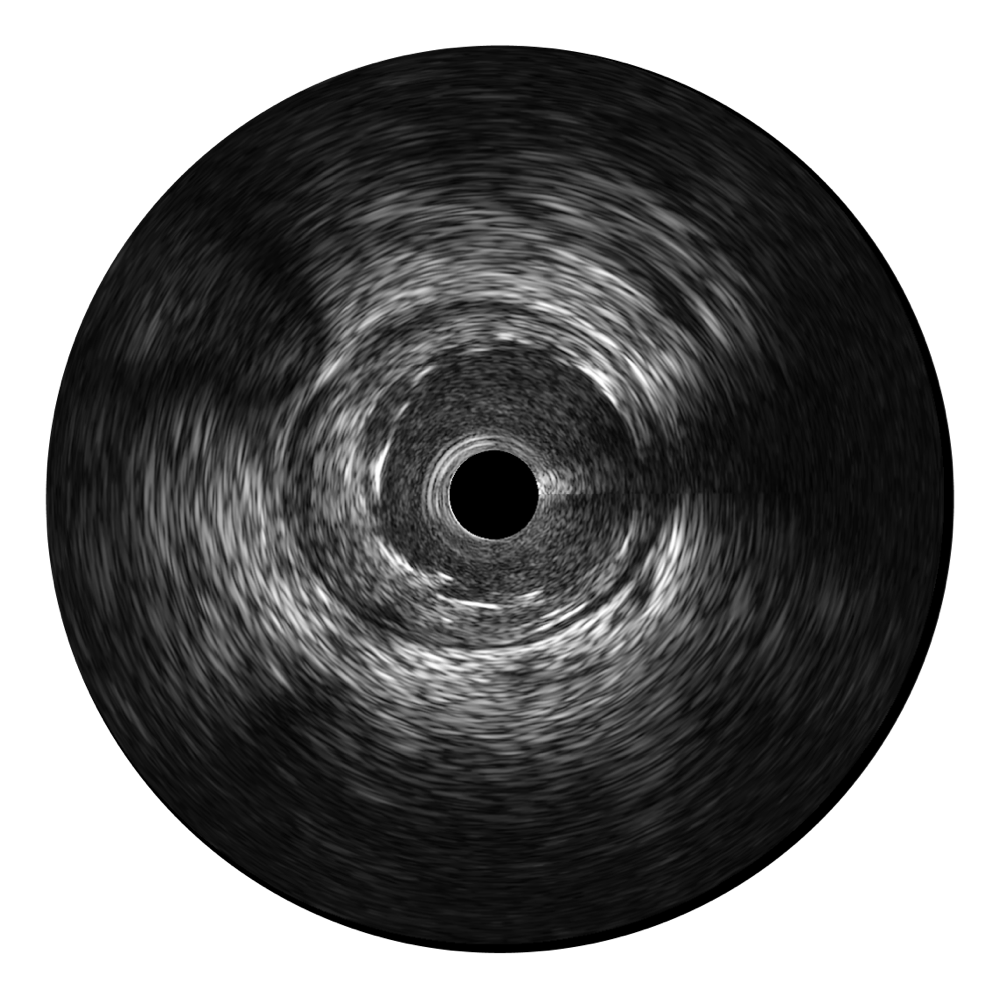

• 诸侯快讯官网宽频IVUS图像

对比传统IVUS导管成像,诸侯快讯官网宽频IVUS图像的近场支架梁显影更细腻,远场中膜外血管仍清晰可辨,兼顾远中近,兼顾分辨力与穿透深度